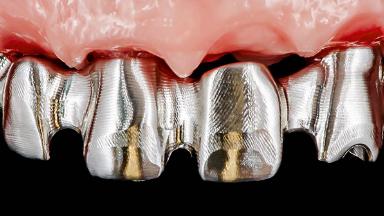

Rehabilitating an Edentulous Maxilla with a Fixed Dental Prosthesis Following Provisional Immediate Loading

This case features the flapless computer-guided placement of 7 bone-level implants, distributed to provide maximal support for the prosthetic framework. A rigid one-piece metallic framework was utilized as an interim restoration to reduce the risk of fracture associated with this prosthetic design. As part of the clinical examination, the SAC Assessment Tool was used, resulting in a surgical and restorative risk classification as “complex”.

Loading Protocol Immediate